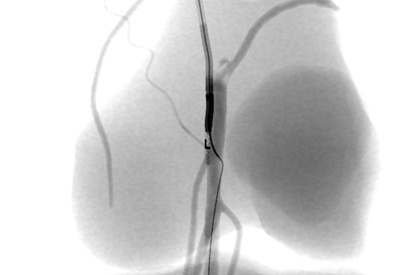

The ANGIO Mentor simulator is an essential tool for clinicians to practice and acquire the skills needed for performing endovascular interventions. Trusted by medical associations, hospitals, training centers, and the medical device industry globally, it provides trainees with realistic clinical settings to practice endovascular interventions using fluoroscopic and ultrasound guidance.

Offers true-to-life simulation of the clinical environment, including advanced imaging modalities like fluoroscopy/echocardiography, hemodynamic monitoring, medications, and interventional devices

Simulates rare and common intra-procedure complications, allowing for realistic training in a safe environment